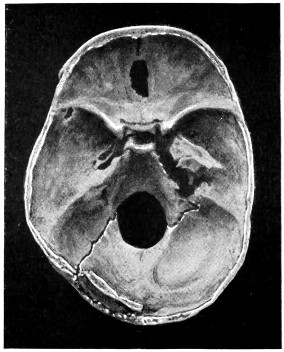

50 A and B. The inner aspect of the skull and the same seen on transillumination 137

51. To illustrate compression of the brain as produced by an extra-dural hæmorrhage from the middle meningeal artery[x] 141

52 A and B. The operative treatment of middle meningeal hæmorrhage 144, 145